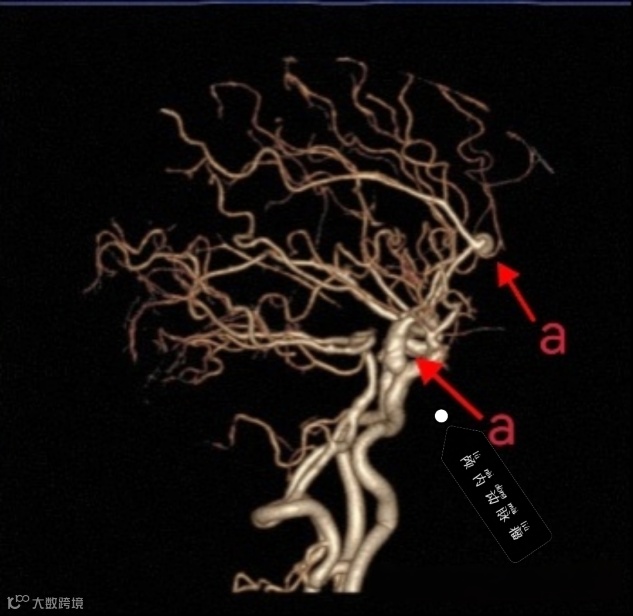

头颈部CTA即头颈部CT血管成像,是经静脉注入含碘造影剂后,经过CT机扫描,通过不同组织对X线的吸收差异,形成不同灰度的图像,再经过后处理软件去除骨及软组织,形成血管三维重建图像。具有快速、无创、并发症少、特异性和敏感性高等特点。

头颈部CTA能够显示脑血管的主干及较大分支,对脑血管疾病起到筛选和初步诊断作用,同时还能显示病变血管周围脑组织的病理性改变。

四、脑血管疾病,如动脉瘤、动静脉畸形、动脉狭窄和闭塞、脑梗塞、脑出血等